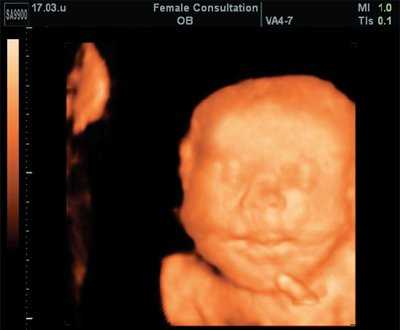

Объем легких теоретически можно оценить в режиме 2D, однако с введением в клиническую практику новых ультразвуковых технологий появилась надежда, что теперь это измерение можно делать точнее и проще. Действительно, использование программы VOCAL (Virtual Organ Computer-aided AnaLysis) позволяет получить фактически виртуальный "слепок" легких (рис. 1). Для этого объем грудной клетки следует получить в 3D режиме в сагиттальной плоскости, когда плод расположен лицом к датчику. Желательно соблюдать следующие правила: датчик слегка наклонить к голове для лучшей визуализации диафрагмы, использовать высокое качество изображения и гармоники, величина угла захвата изображения от 40 до 85º в зависимости от срока.

Рис. 1. Реконструкция здорового правого легкого и расчет его объема с применением программы VOCAL.